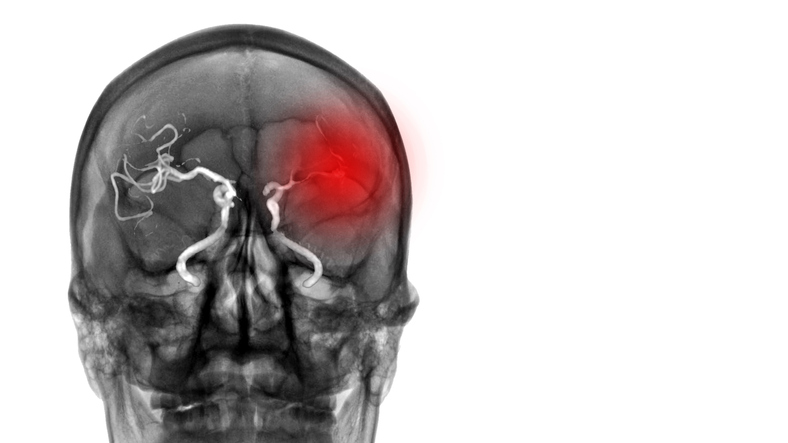

Mieux prédire les suites d’un traitement endovasculaire après un AVC ischémique

Des chercheurs ont développé et

validé un modèle de prédiction des résultats fonctionnels pour les patients

après un traitement endovasculaire d’un AVC ischémique. Ce modèle a été élaboré

à partir des données individuelles de patients inclus dans 7 essais cliniques

randomisés, menés entre 2010 et 2014. Au total, 19 variables ont été évaluées

pour prédire le résultat fonctionnel du traitement endovasculaire à 90 jours.

Toutes ces variables étaient accessibles dès le lendemain du traitement

endovasculaire. Sur ces 19 variables, 9 ont été incluses dans le modèle, dont

l’âge, le score NIHSS, le score mRS avant l'AVC, les antécédents de diabète, la

localisation de l'ischémie, le score collatéral, le grade de reperfusion, le

score NIHSS à 24 heures et l'hémorragie intracrânienne symptomatique 24 heures après

le traitement endovasculaire.